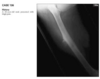

23 year old man with pain in the right hip

An anteroposterior view of the pelvis

shows flaring of the metaphyseal regions of

the proximal femurs and numerous osteochondromas

arising from the right iliac crest, pubic bones, and proximal right femur (arrows).

Axial CT through upper pelvis - Large right exostosis with soft tissue mass.

AP radiograph of knee - multiple osteochondromas arising from femur and fibula.

DIAGNOSIS: Multiple hereditary exostosis

AD disorder age 10-20s

Signs of malignant transformation - Growth of previous stable exostosis, new or increasing calcifications, new bony erosion

Associated with chondrosarcoma